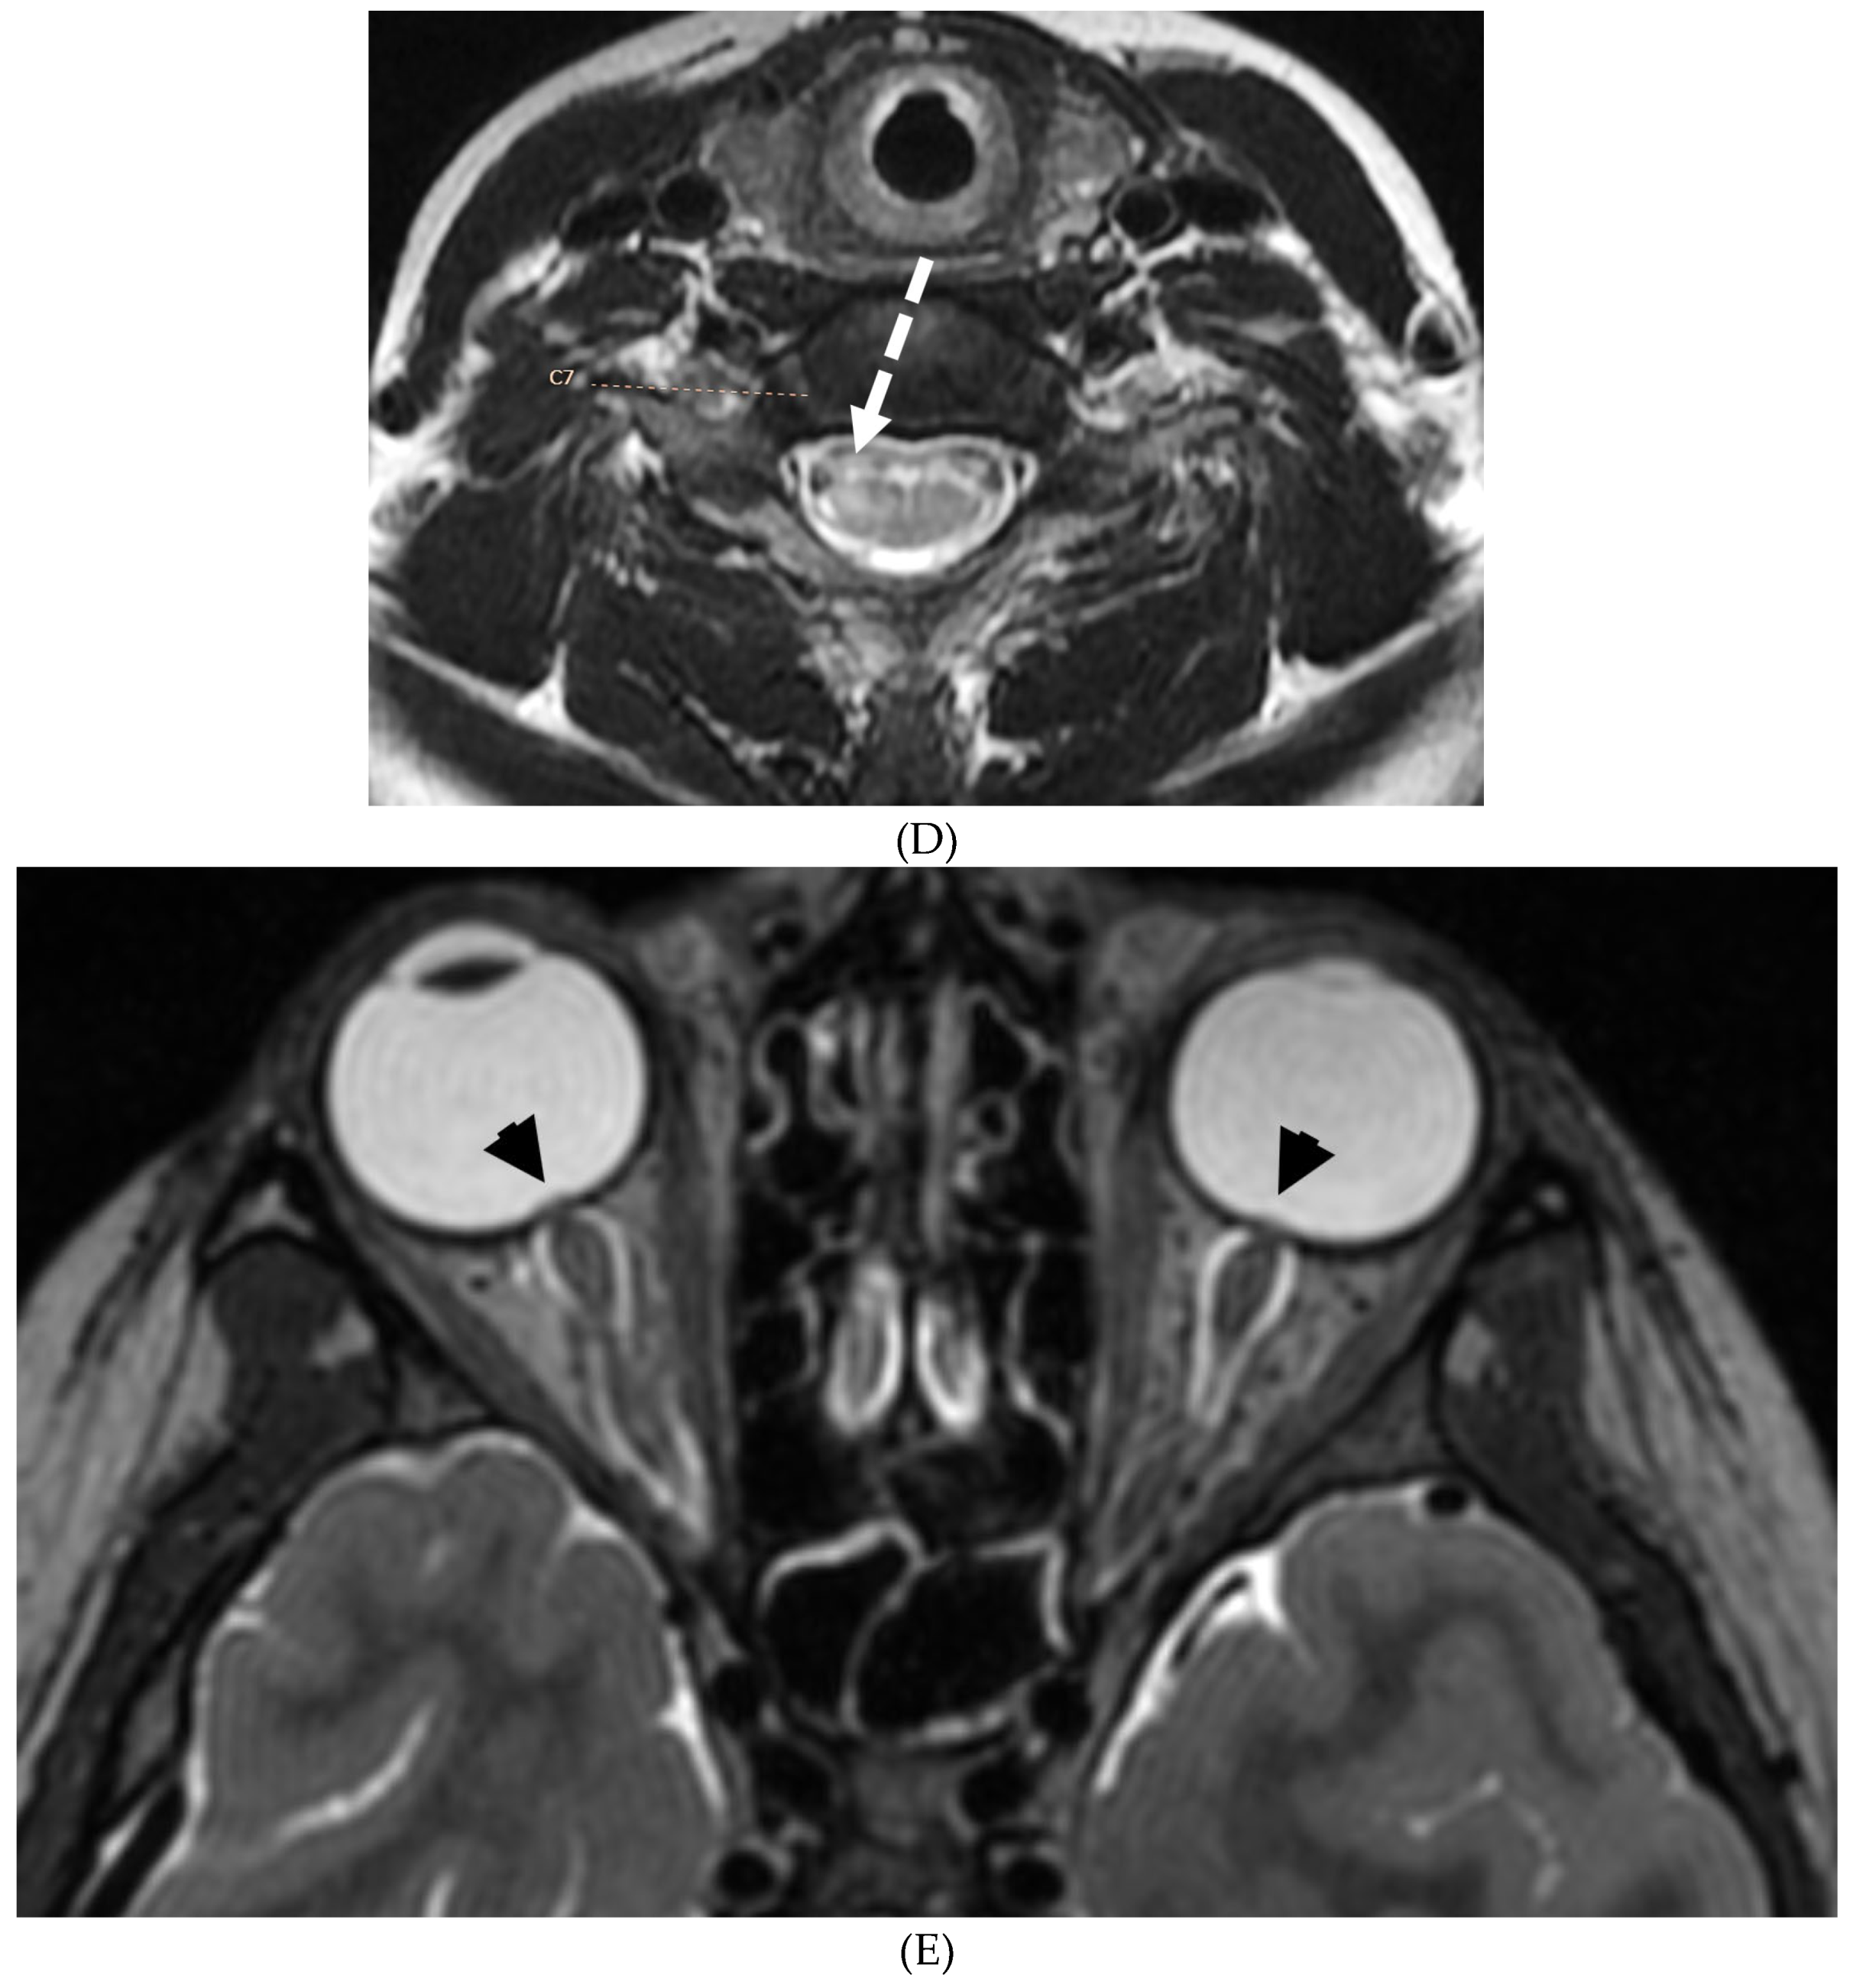

GUILLAIN BARRE SYNDROME

- Alkan O, Yildirim T, Tokmak N, Tan M. Spinal MRI findings of guillain-barré syndrome. J Radiol Case Rep. 2009;3(3):25-8. Epub 2009 Mar 1. PMID: 22470650; PMCID: PMC3303301. [CrossRef]

- Zuccoli G, Panigrahy A, Bailey A, Fitz C. Redefining the Guillain-Barré spectrum in children: neuroimaging findings of cranial nerve involvement. AJNR Am J Neuroradiol. 2011 Apr;32(4):639-42. Epub 2011 Feb 3. PMID: 21292802; PMCID: PMC7965877. [CrossRef]

- Yikilmaz A, Doganay S, Gumus H, Per H, Kumandas S, Coskun A. Magnetic resonance imaging of childhood Guillain-Barre syndrome. Childs Nerv Syst. 2010 Aug;26(8):1103-8. Epub 2010 Jun 17. PMID: 20556395. [CrossRef]

- Byun WM, Park WK, Park BH, Ahn SH, Hwang MS, Chang JC. Guillain-Barré syndrome: MR imaging findings of the spine in eight patients. Radiology. 1998 Jul;208(1):137-41. PMID: 9646804. [CrossRef]

- Malhotra A, Zhang M, Wu X, Jindal S, Durand D, Makhani N. MRI findings of optic pathway involvement in Miller Fisher syndrome in 3 pediatric patients and a review of the literature. J Clin Neurosci. 2017 May;39:63-67. Epub 2017 Feb 10. PMID: 28209311. [CrossRef]